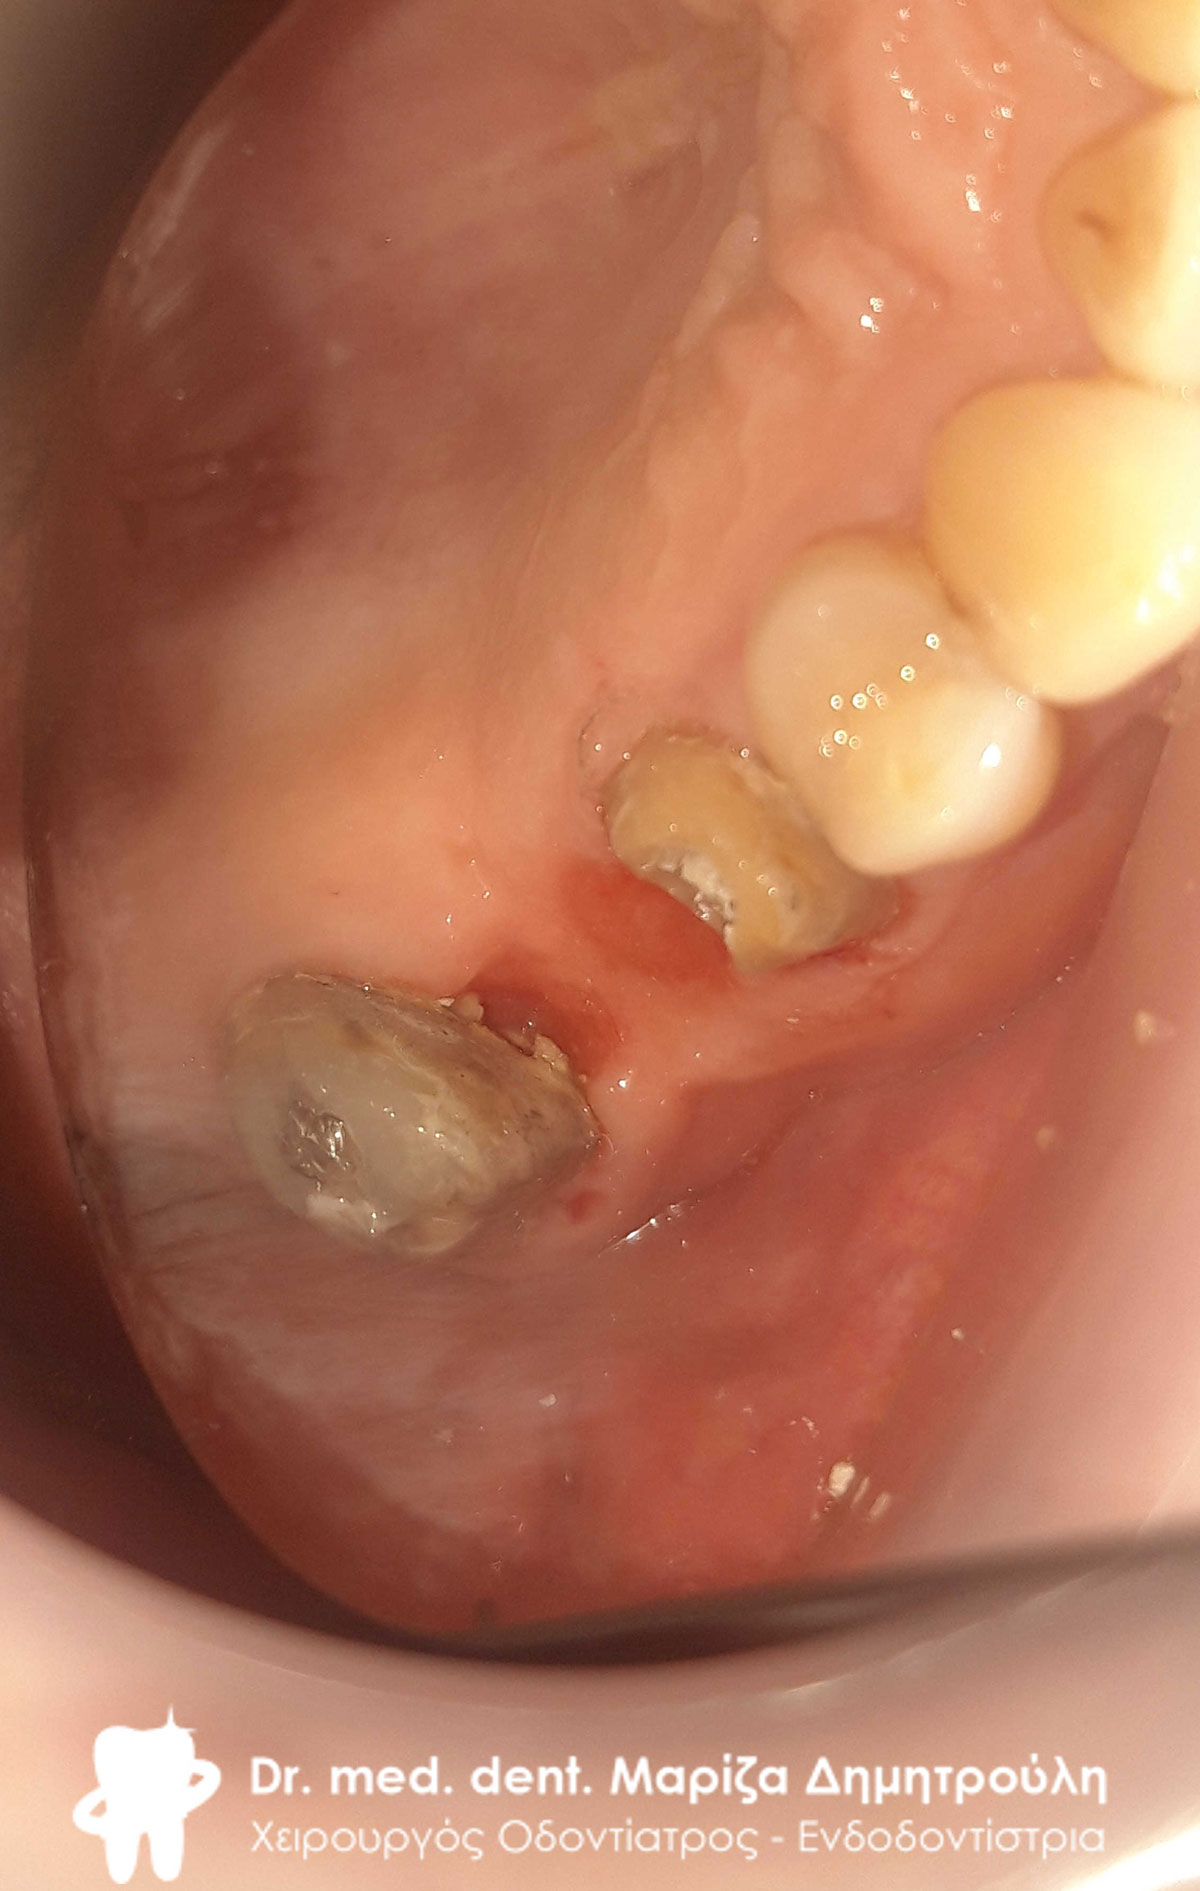

Αρχική κλινική εικόνα του μεγάλου οδοντικού ελλείμματος

Στη συγκεκριμένη ασθενή πραγματοποιήθηκε απονεύρωση δοντιού. Το οδοντικό έλλειμμα ήταν μεγάλο, οπότε το δόντι μετά την απονεύρωση έπρεπε να αποκατασταθεί είτε με θήκη δοντιού είτε με ολοκεραμικό ένθετο. Τελικά αποφασίστηκε η αποκατάσταση με ένθετο δοντιού, γιατί χρειάστηκε να θυσιαστεί λιγότερη οδοντική ουσία. Η ασθενής είναι ευχαριστημένη τόσο με τη λειτουργικότητα όσο και με το αισθητικό αποτέλεσμα.